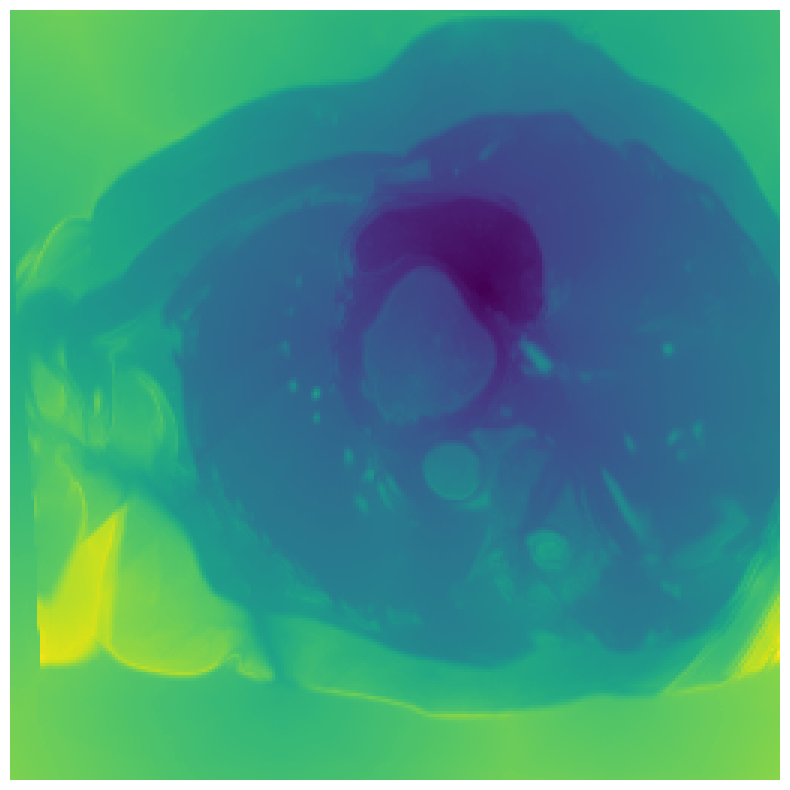

Generally, given an exact, full annotation of an object, such a Euclidean signed distance map encodes also information on the shape of an object. But when using a weak ground truth , where and , inferring a correct extent and shape of the objects is nontrivial. As shown in 1(b), Euclidean distance calculated from a point label source grows radially, regardless of the actual shape of the object, and thus makes little sense from an information point of view. Under the assumption of intra-object homogeneity and inter-object contrast (w.r.t intensities), this problem can be circumvented to a degree by using a distance function that takes also intensity values into account. An example of a commonly used distance measure with an intensity component is the Geodesic distance ([34]). Let denote a path between , with and being neighbors under a chosen adjacency relation. Reusing the notation from before, a Geodesic distance map from the boundary of the ground truth class , , can be defined as

Both the Intensity and the Minimum barrier distance are defined exclusively on the image intensity space. However, from the examples of distance map in 1(d), we can notice that the values still increase somewhat radially from the annotation. This behaviour is similar to the one of the Geodesic distance in 1(c) (which actually includes the spatial proximity in its definition), and is due to the summing operator in the general Geodesic distance definition in Equation 3. While the intensities of two neighboring pixels on a path may be the same, that will rarely be the case in real life, noise riddled images. This makes the Intensity distance function approximately monotonically increasing with increasing length of the path (in space), even on paths where the intensity is mildly fluctuating (e.g. consider a path with even pixels intensity value of and odd pixels intensity value of ). One could thus argue that such a definition of a distance, despite being based exclusively on intensities, is still capable of loosely encoding the spatial distance information.

On the other hand, while we can see that the MBD based maps are similar to Geodesic and Intensity ones (1(e)) with respect to the object shape recovery, they have a less pronounced and smooth increase in the values outward from the source point.

In contrast to Euclidean distance, the Geodesic, Intensity and Minimum barrier distance maps all encode contrast sensitivity and preserve the object structures by harnessing the intensity information of the underlying image. This holds even when calculated from point sources. In practice, using such maps for network training could mean a lower penalty for false positives that occur farther from the point annotation but are close to it in intensity. Thus still enabling the propagation of a sort of shape information (as it can be inferred from the raw image intensities).

We normalize the volumes and resize the slices to pixels. As the official dataset comes with full annotations, we create a synthetic point ground truth. This is done by first randomly choosing the centers of the point annotations within the class masks, followed by filling an ellipse with axes lengths of and (in pixels) around each center. The intersections of these elliptic discs with the underlying full annotations are then used as our point ground truth. See Figure 2 for an example of the created weak annotation mask. The point annotations are created for every slice, one for each foreground object present in the slice.

In Figure 6 we provide qualitative results on a number of randomly chosen test set slices. Upon visual inspection, we can observe that training with the intensity-aware distances (particularly with and ) follows the image gradients better and is better at recovering the underlying shape than the Euclidean version. The CRF-loss seems to recover the shape of the myocardium and left ventricle to some extent, but fails entirely on the right ventricle.